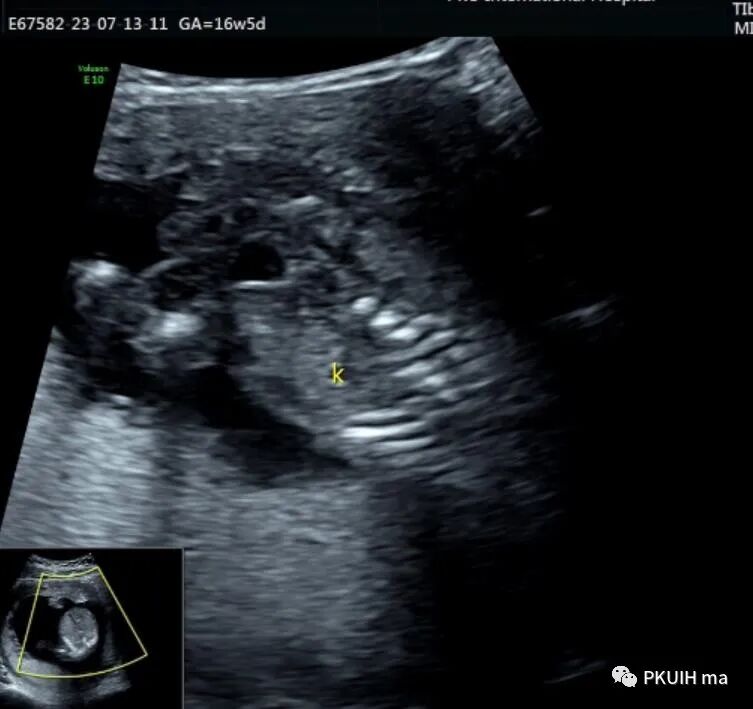

观察囊肿与肾、胃泡、膀胱均无相关。

仔细观察囊肿壁好像不完整,周边见微小管道回声与囊肿相通

由于囊肿位于胆囊后方、肝下方、门静脉窦旁,随考虑为胆总管囊肿